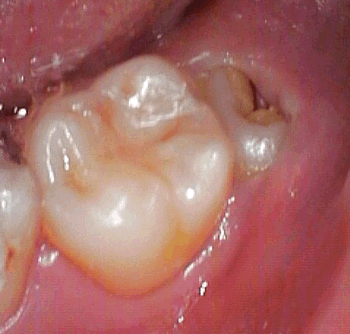

この方は、比較的真直ぐな親知らずですが、歯茎に埋もれて虫歯もあります!

痛いので抜いて欲しいと週末に来られたのですが、、、 |